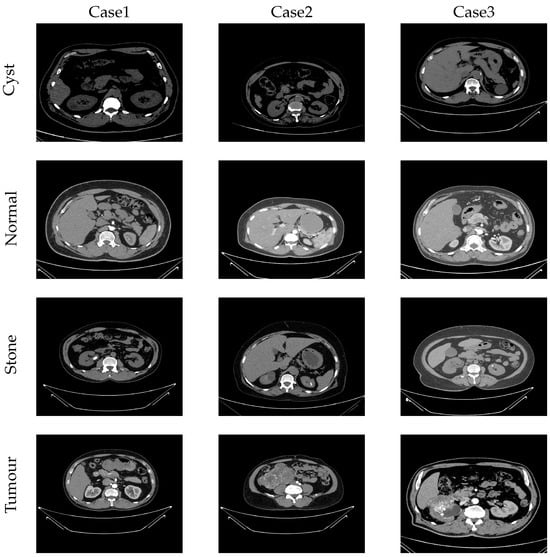

4.2. Used Dataset